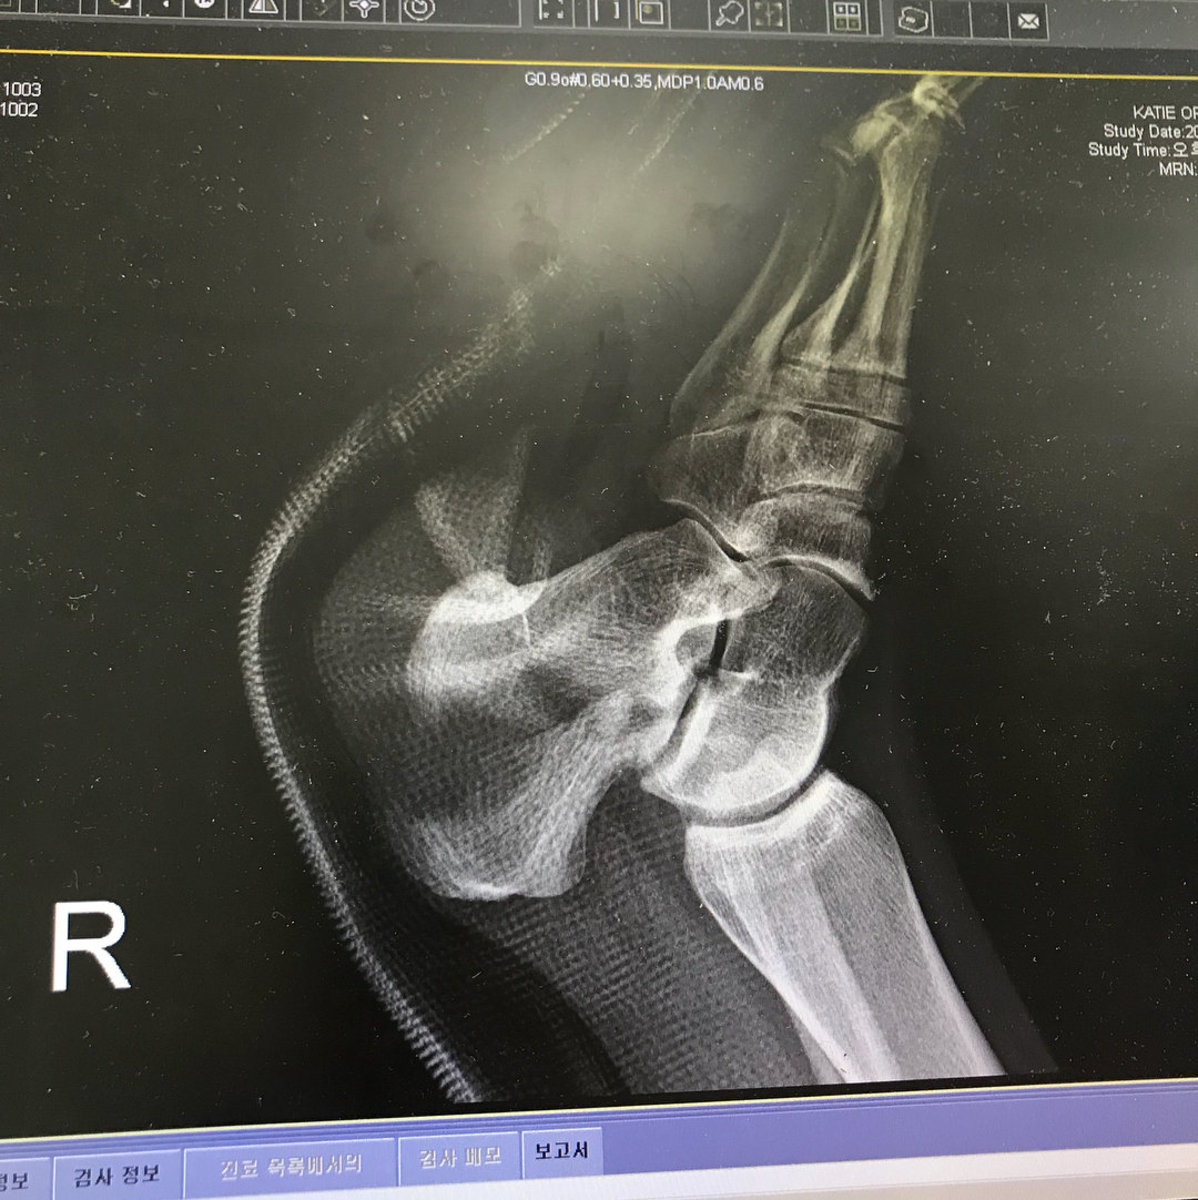

British snowboarder Katie Ormerod is seen in hospital after fracturing her wrist and heel in training, in Seoul, South Korea, February 9, 2018. REUTERS/Instagram/Omerodkatie

Image showing British snowboarder Katie Ormerod's injury after fracturing her wrist and heel in training, in Seoul, South Korea, February 9, 2018. REUTERS/Instagram/Omerodkatie